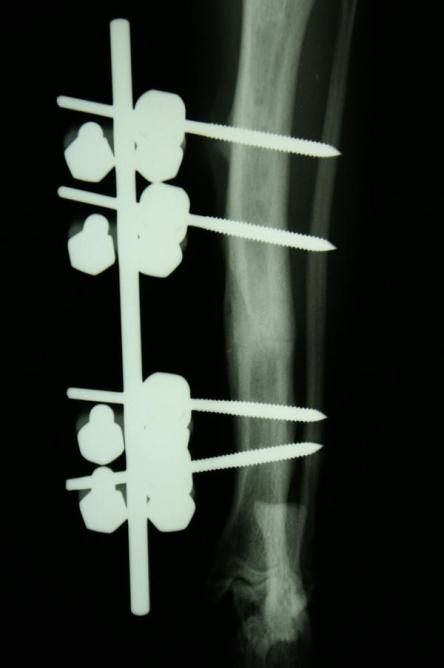

Auf dem Röntgenbild des Beines ist erkennbar, dass das Schienbein in der Mitte quer gebrochen ist. Feine Haarrisse ziehen von der Frakturspalte kniewärts. Das Wadenbein ist intakt, was die relative Stabilität des Bruchs erklärt.

Die Fraktur ist auf Dauer konservativ nicht ausreichend stabilisierbar. Hierzu müsste das Gelenk ober- und unterhalb des Bruchs (d.h. Knie- und Sprunggelenk) immobilisiert werden, was aufgrund der Anatomie eines Katzenbeines nicht möglich ist. Zusammen mit den Besitzern wird entschieden, den Bruch mit einem sogenannten Fixateur Externe zu versorgen.

Nach vier Tagen wird nochmals ein Röntgen des Brustkorbs angefertigt, auf welchem erkennbar ist, dass sowohl Lungenblutung als auch Pneumothorax verheilt sind und eine Narkose somit möglich ist. Je zwei Stahlstifte werden ober- und unterhalb der Bruchstelle durch die Haut in den Knochen gebohrt und ausserhalb des Körpers mittels Klampen, Muttern und einem Verbindungsstift verbunden, was zusammen mit der stabilisierenden Wirkung des Wadenbeins eine ausgezeichnete Fixation ergibt. Der ausserhalb der Haut liegende Teil dieser Konstruktion wird mit einem gepolsterten „Verband“ umgeben, damit die Katze mit den Metallteilen nicht an Gegenständen hängen bleibt.

„Pfüdi“ belastet nach der Operation das Bein sofort wieder sehr gut, muss aber zur besseren Heilung 6 Wochen in seiner Bewegung eingeschränkt werden. Nach dieser Zeit wird ein Röntgenbild angefertigt, welches zeigt, dass die Fraktur sehr gut verheilt ist. Der Fixateur Externe wird in einer kurzen Narkose entfernt.